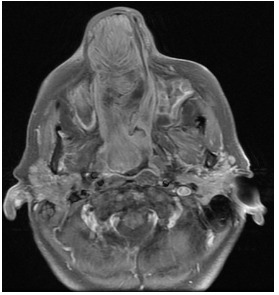

En secuencia T2 sin contraste, la lesión presenta áreas hiperintensas y de baja señal, determinando marcado desplazamiento del tabique nasal y oblitera trompa de Eustaquio derecha, con ocupación de celdillas mastoideas y oído medio homolaterales (Figura 8–9-10).